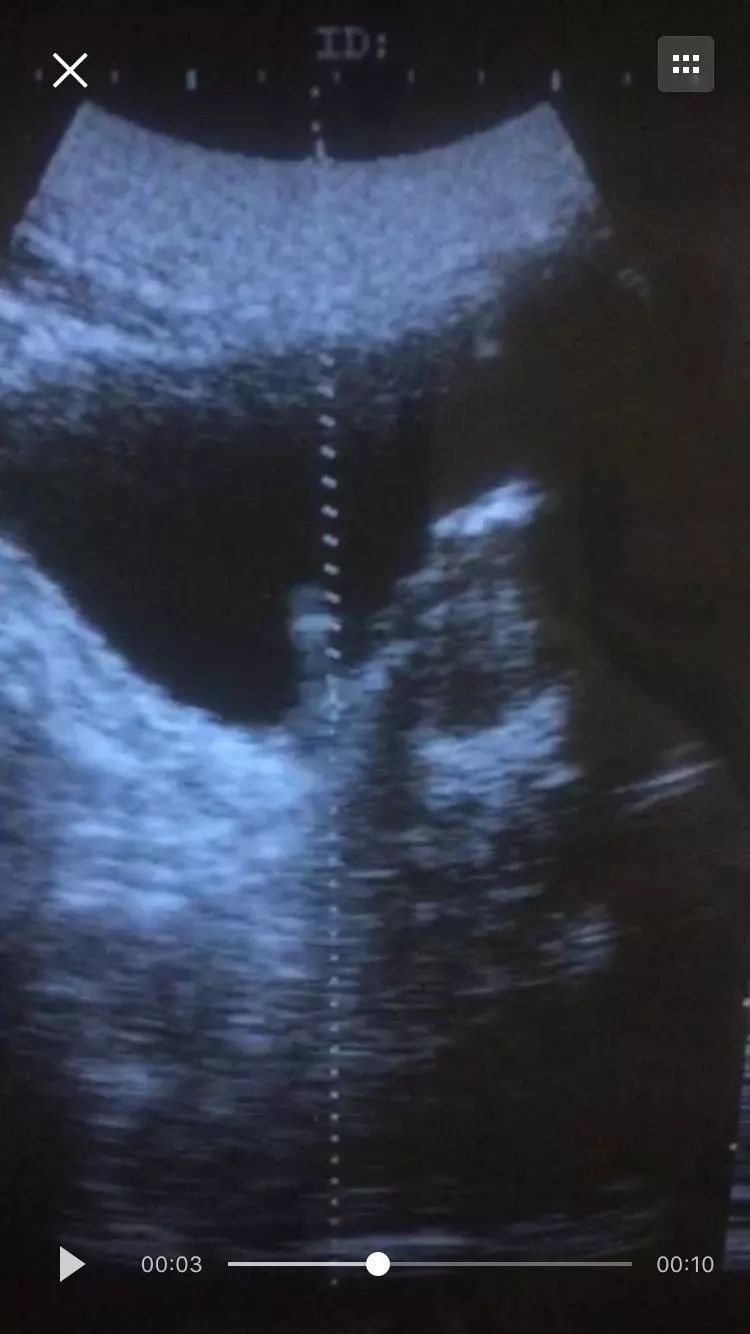

崇州长征医院采用新一代体外冲击波碎石机,20分钟就能轻松碎石,成功率高达99.98%,下面是我院一位碎石病人术前术后的B超对比图

男性55岁患者,入院前已有10年的右侧腰腹部疼痛史,在外院输液治疗未果,疼痛却明显加剧,还伴有恶心呕吐等不适症状,来我院检查发现发现右侧输尿管有花生粒大小结石,通过体外冲击波碎石治疗后成功碎石。